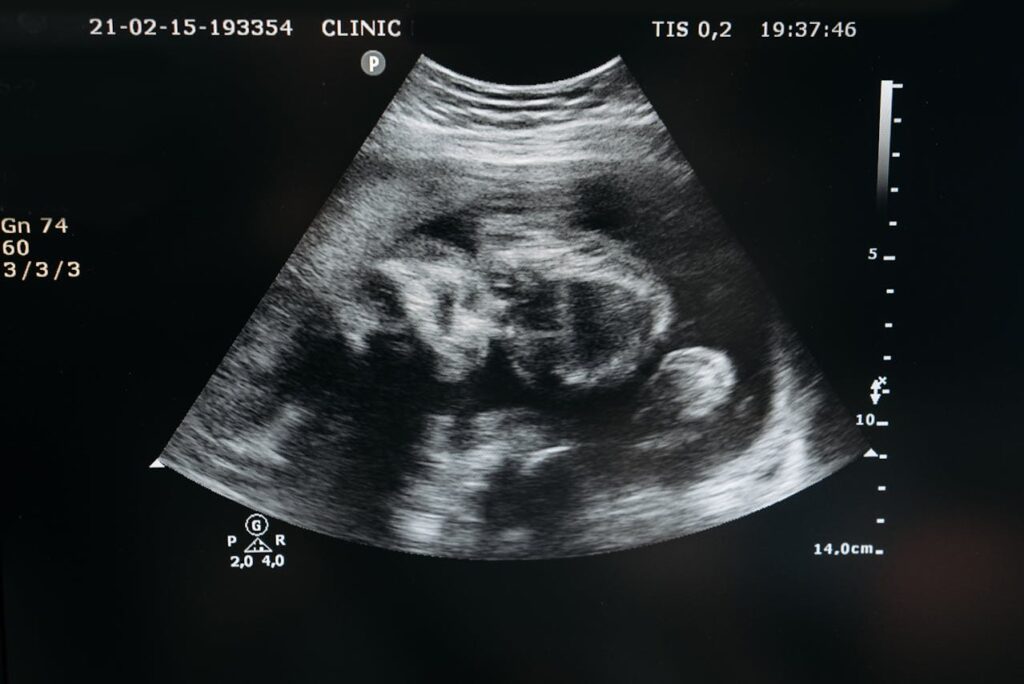

Actualmente entre la semana 11-13s y formando parte del test combinado (cribado de cromosomopatías, por ejemplo síndrome de Down) se debe realizar a todas las gestantes una evaluación ecográfica fetal exhaustiva con la finalidad de hacer una primera valoración morfológica fetal y evaluar varios marcadores ecográficos de cromosomopatías (Translucencia nucal).

En nuestro servicio esta exploración se realiza de forma centralizada, con ecógrafos de gama alta y con personal especializado en este tipo de ecografía con la finalidad de obtener la mejor evaluación posible. Se sigue una evaluación ecográfica de las 11-13 recomendada por la international society of ultrasound in obstetrics and gynecology (ISUOG).